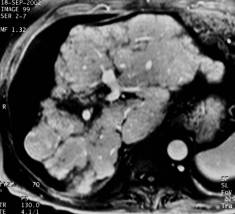

Patient suivi pour une cirrhose alcoolique. L'IRM est réalisée dans le cadre d'un bilan pré greffe.adressé pour bilan pré greffe.Vascularisation

Séquence pondérée T2, T1 Injection de gadolinium phase artérielle portale et tardive à 5 mn |

Vascularisation hétérogène du foie : nudule hypervasculaire à la phase artérielle (CHC), réhaussement locorégional à la phase portale ( vol vasculaire) et rehaussement tardif de la fibrose confluente (zone atrophique du segment V).